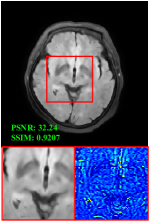

Figure 5 provides the qualitative comparison of the various methods on the four datasets at a scale of 4. The top, second, third, and bottom rows are the SR results under the FastMRI, clinical brain, clinical tumor and clinical pelvic datasets, respectively. The red boxes indicate the zoom-in region of complicated anatomical structures along with their corresponding error maps. Note that the brighter textures in the error maps, the lower the quality of the reconstructed images. As can be seen, compared to methods based on Transformers and CNNs, diffusion-based methods like DisC-Diff and DiffMSR (Ours) are capable of reconstructing high-realistic images with promising reconstruction metric scores (PSNR and SSIM). Nevertheless, while DisC-Diff can reconstruct high-precision MR images, it does not preserve the structure present in the original HR images, introducing some additional information that can affect medical diagnosis. In contrast, our method combines DM and PLWformer, which can preserve the original image’s structure while restoring high-frequency information.

In this section, we present more visual qualitative comparisons. Figures 8, 9, 10, and 11 show the reconstruction results of each method in FastMRI, clinical brain, clinical tumor, and clinical pelvic, respectively. As can be seen, although DisC-Diff can reconstruct MR images with high-frequency information, it fails to preserve the structure and content of the original Target HR image effectively, resulting in image distortion. In contrast, our proposed DiffMSR can restore high-frequency information while preserving the structure of the original HR image, indicating the effectiveness of the joint use of DM and PLWformer.